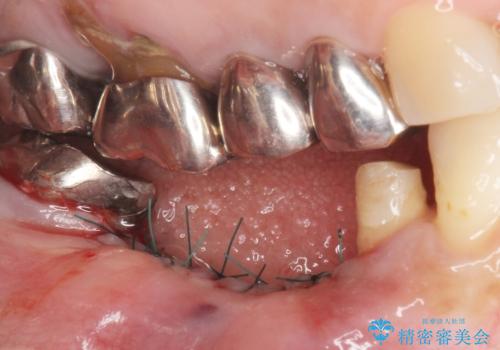

保存不可能な歯を抜去後、インプラント治療と根管治療を行いました。

他にも予後不良な歯があり治療を提案しましたが、ご予算もありご希望されませんでした。

インプラントへの悪影響に関しても説明し、了承頂いた上で治療を行いました。